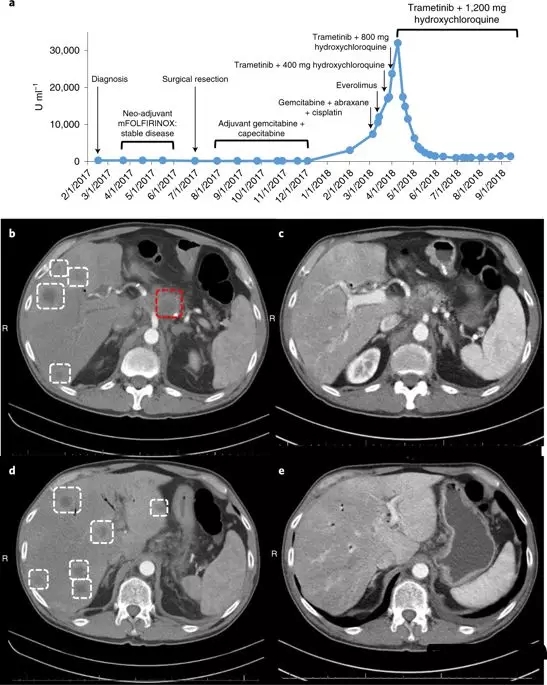

这种联合疗法的效果在一位晚期胰腺癌患者身上同样得到了证实,这位患者在手术后,接受了几次化疗,但不幸的是癌症复发并转移了,目前已经没有很好的治疗方案,

这名患者接受了trametinib和hydroxychloroquine治疗,令患者和医生震惊的是,奇迹出现了,2个月内,患者的胰腺癌标志物CA19-9的血液水平下降了95%。4个月后,他体内的癌症数量减少了50%。

对于胰腺癌来说,这是一个非常了不起的反应!

用曲美替尼加羟氯喹(T/HCQ)治疗胰腺癌患者导致肿瘤标志物癌抗原19-9(CA19-9)和总体肿瘤负荷减少。